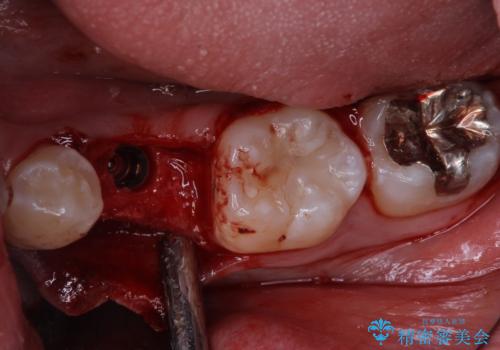

- 乳歯を抜歯したところにインプラントをしたいと来院された患者様です。

永久歯の先天欠如による乳歯の晩期残存があり、その乳歯が虫歯になってしまい保存不可能になり、他院で抜歯をし義歯を使用していた状態です。

義歯では嚙みづらいため、インプラントによる補綴をしていくこととしました。

- 外科手術のため、術後に痛みや腫れ、違和感を伴います

- メンテナンスを怠ったり喫煙により、お口の中に大きな悪影響を及ぼすインプラント周囲炎等にかかる可能性があります